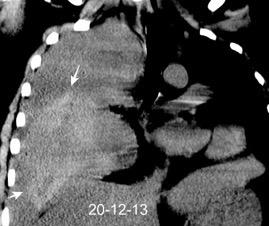

Afectación transdiafragmática: 5,6-43,7% de quistes hepáticos. “Área desnuda” del hígado.

Panda A et al. “Straddling Across Boundaries”. Thoracoabdominal Lesions: Spectrum and Pattern Approach. Curr Probl Diagn Radiol. 2015 Área desnuda. El hígado en contacto directo con el tendón central del diafragma. Contiene el hiato de VCI.